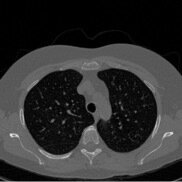

Conditional Samples (Poisson vs Gaussian DPS)

DPS:

\[\nabla_{x_t} \log p(y \mid x_t) \approx \nabla_{x_t} \log p(y \mid \hat{x}_0(x_t))\]

Poisson

Gaussian